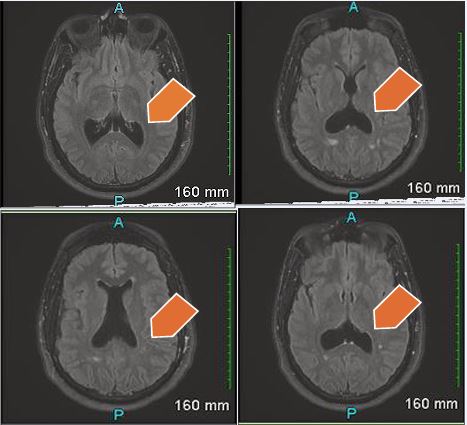

Figure B MRI Brain with contrast – Hypoplasia of the septum pallucidum. Corpus callosum is intact. Trace scattered white matter disease primarily in the parietal lobe. There is enlargement of the posterior horns of the lateral ventricles, suggesting colpocephaly.

A subsequent contrast-enhanced MRI (Figure B), confirmed hypoplasia of the septum pellucidum with mild colpocephaly and an intact corpus callosum. Additionally, there was scattered white matter disease in the parietal lobes without abnormal enhancement. The ventricular findings were unchanged from the prior study.